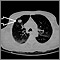

TC torácica

Es un método imagenológico que utiliza rayos X para crear imágenes transversales del tórax y la porción superior del abdomen.

La tomografía computarizada (TC) crea rápidamente imágenes detalladas del cuerpo, incluyendo el cerebro, el tórax, la columna y el abdomen. El examen se puede utilizar para visualizar mejor las estructuras dentro del tórax.